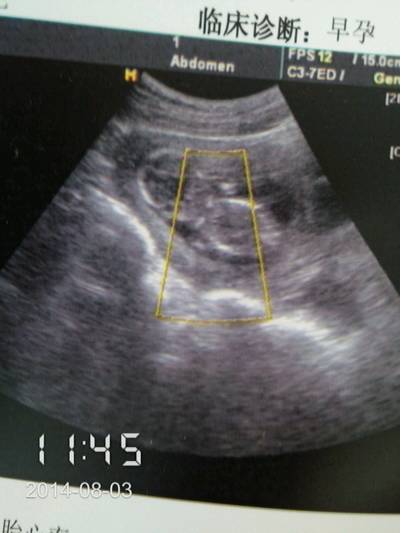

很想知道是男孩还是女孩,第一个男孩女孩我都喜欢就是想早点做准备可以帮我看吗

b超虽然可以看出来,但是给你的报告只是很多图片中的一个,不会给你能看性别的,因为是违法的